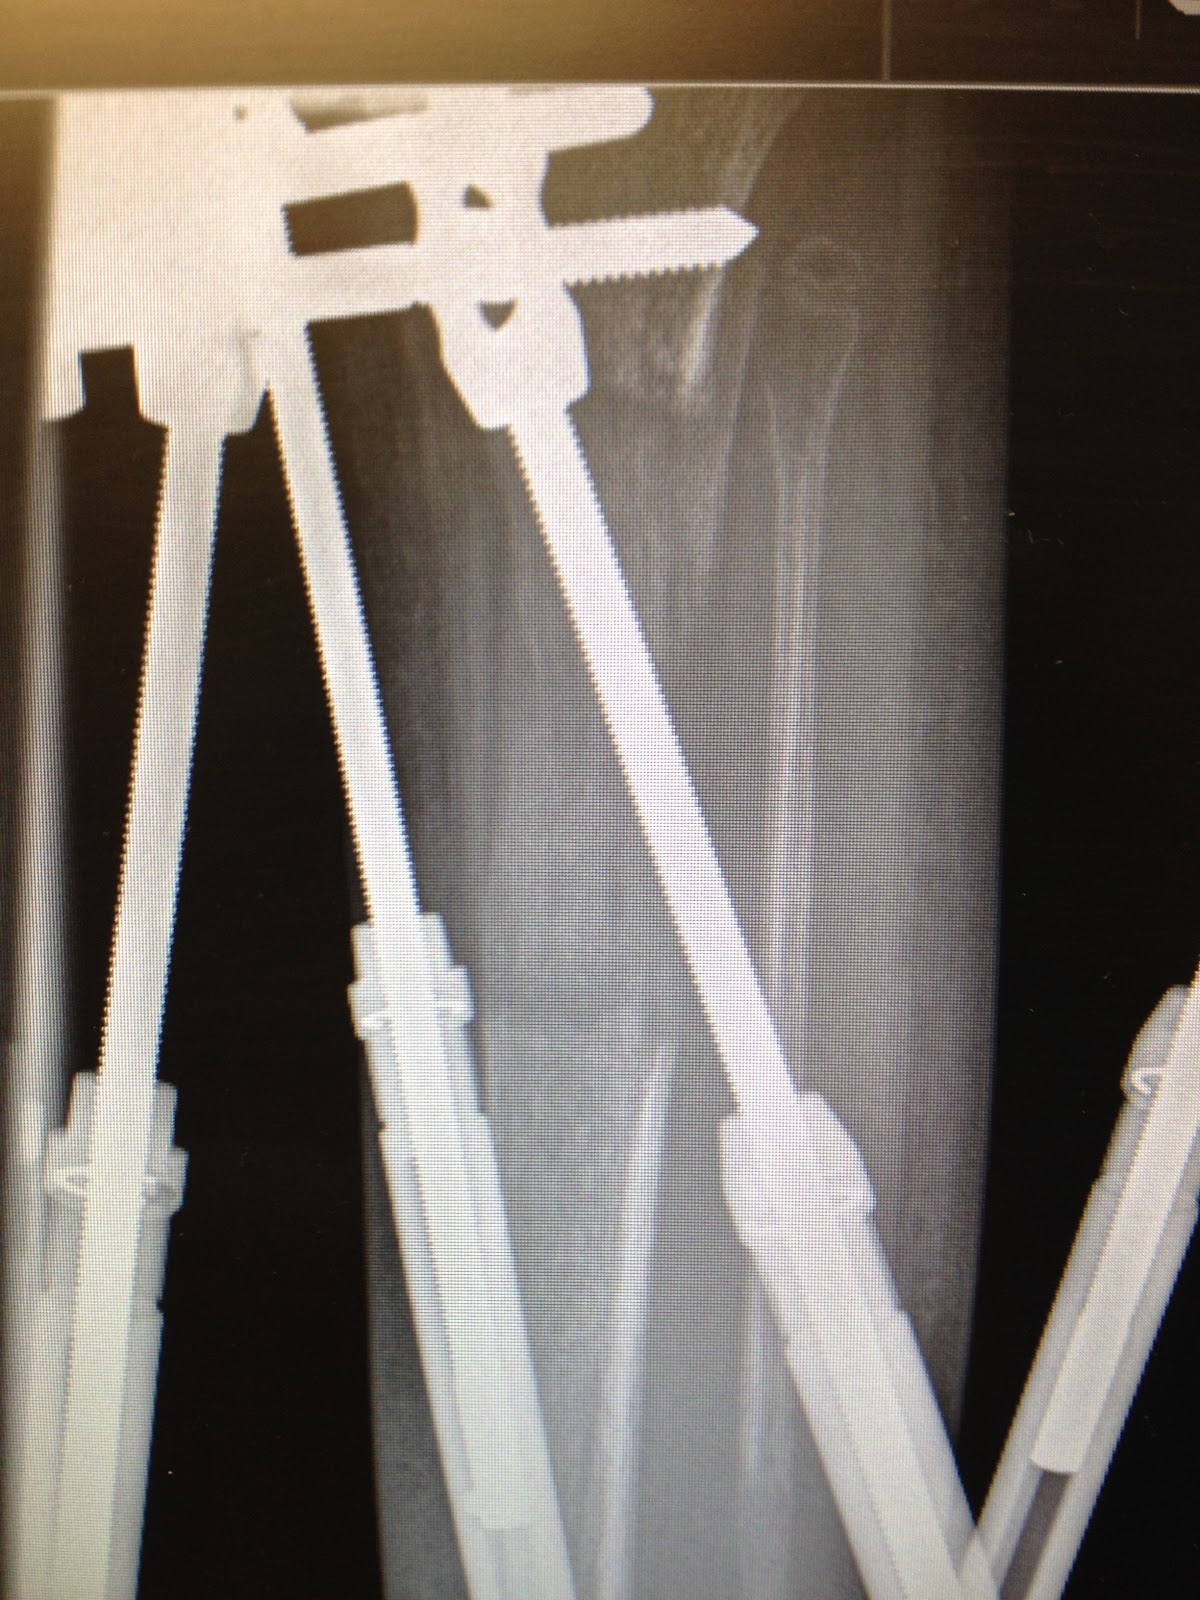

| No blue wires- down to 4 pins (from 16 pins & wires) |

Mary's tibia had "sagged" (the area of her bone that was cut on May 10 sunk in back towards her calf) so he adjusted the struts to correct the sag and decreased the struts by 3 mm.

He put the strut he removed on August 20 back in because of the sag in the tibia.

The removal of the blue wires allows some torque with the fixator but the new bone growth compensates for the torque. Some torque is good because it stimulates bone growth.